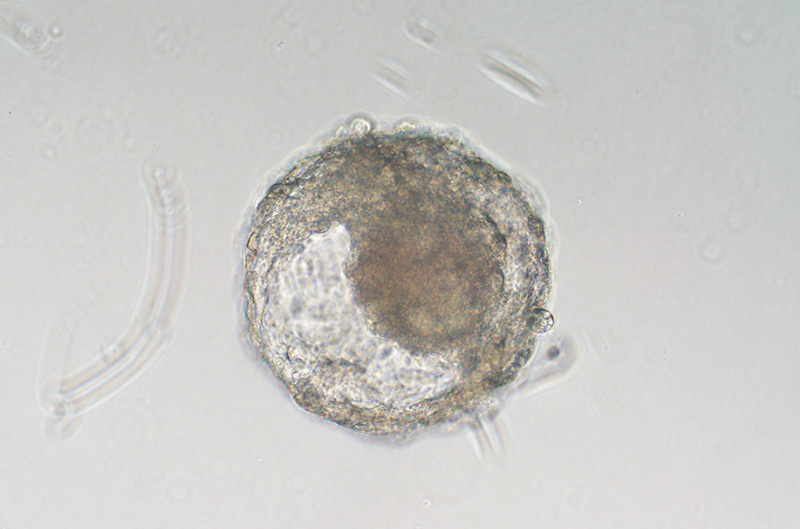

Researchers in China grew this embryolike ball of cells, known as a blastoid, from monkey embryonic stem cells. The researchers were the first to produce monkey blastoids, which could serve as good models of early human development.ZHEN LIU

Monkey blastoids promise to be better models, but the right recipe for culturing them proved elusive. Now, Zhen Liu of the Chinese Academy of Sciences and colleagues have generated blastoids from the embryonic stem cells of cynomolgus monkeys, they report today in Cell Stem Cell. The researchers raised the cells in 3D cultures and coaxed them to divide and specialize with two kinds of media. In culture, the blastoids could survive about 18 days.

They developed further than any previous blastoids, undergoing gastrulation, the cellular reorganization that sets up the three basic layers of the embryo. They also contained many of the same types of cells genuine monkey blastocysts do and showed similar patterns of gene activity, suggesting they were faithful replicas.